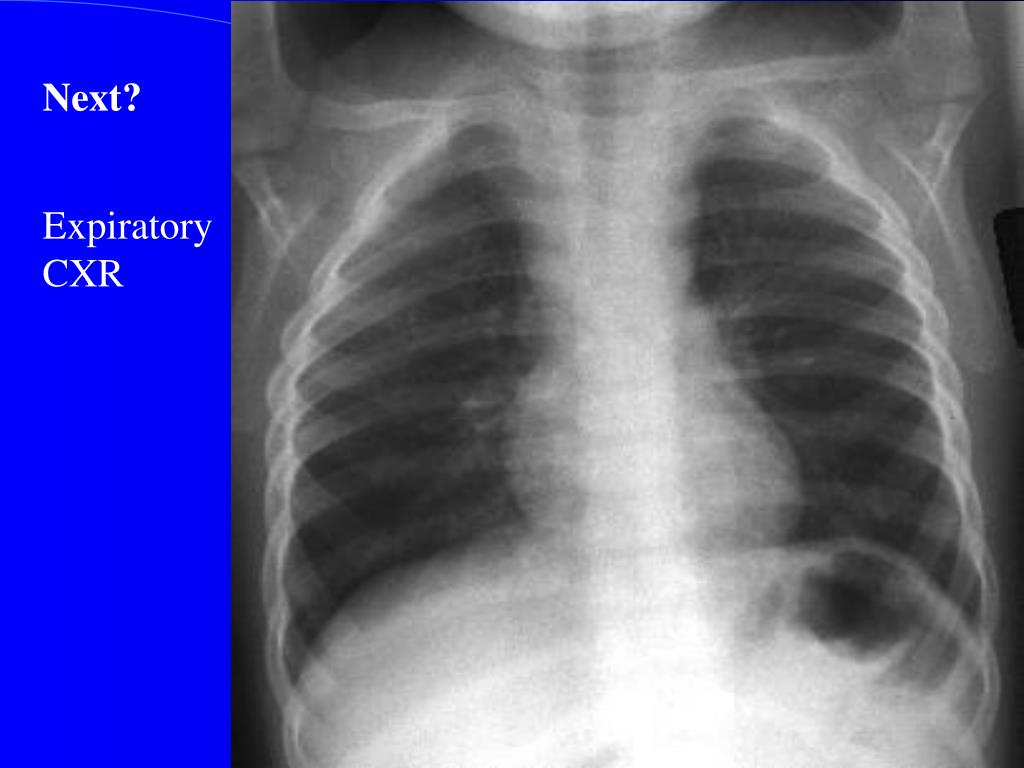

29. Next? Expiratory CXR

30. Inspiratory View Expiratory View

34. Investigations • Xrays • Lateral neck • Chest – inspiratory, expiratory, decubitus views • Expiratory views • Overinflation (partial obstruction with inspiratory flow) • Volume loss with mediastinal shift towards obstructed • side (partial obstruction with expiratory flow) • Atelectasis (complete obstruction)

35. Decubitus views Normal Smaller volumes and elevated diaphragm on side down Abnormal Hyperinflation or “normal” volumes in decub position If suspected … Need a bronchoscope to rule out or remove Foreign Body